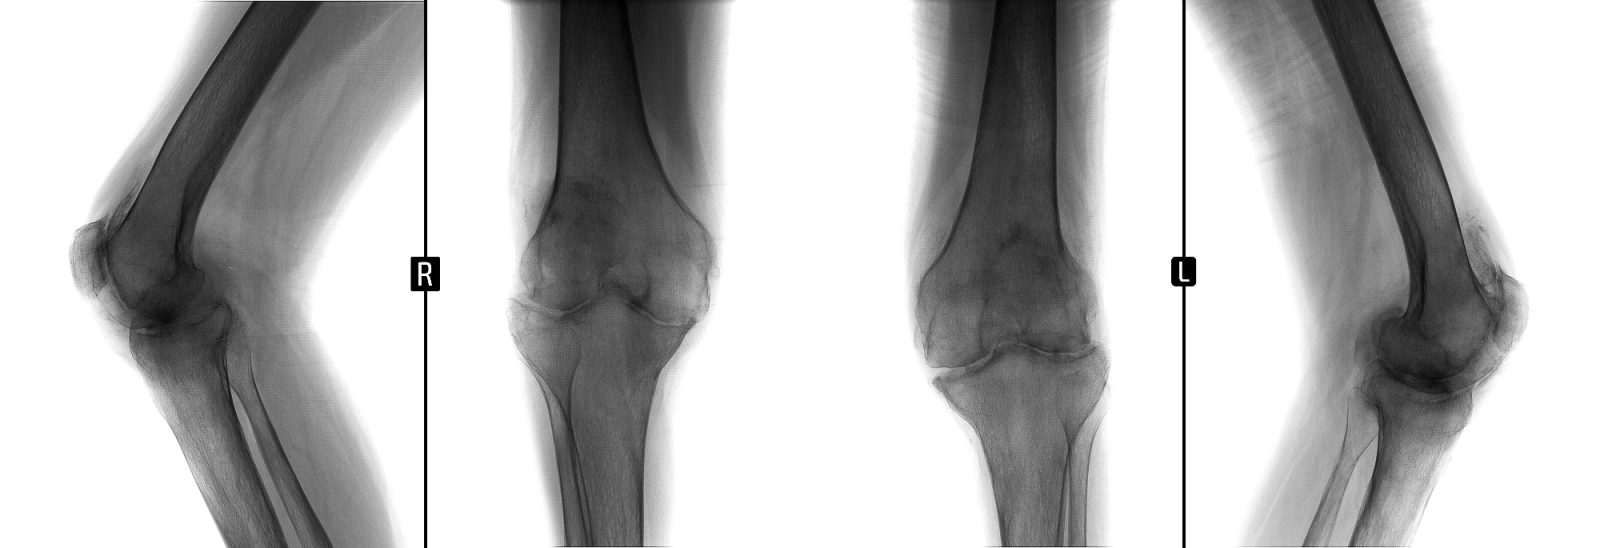

Ko nastopi artroza kolena, pride v končni fazi tudi lahko  do zamenjave kolena

Kadar se sklepni hrustanec v kolenskem sklepu obrabi, nastane artroza kolena, ena najpogostejših degenerativnih bolezni. Zaradi obrabe hrustanca sklep ne drsi več gladko, kar povzroča bolečine in omejeno gibljivost kolena. Najpogosteje se artroza kolena pojavi pri starejših, izjemoma pa tudi…